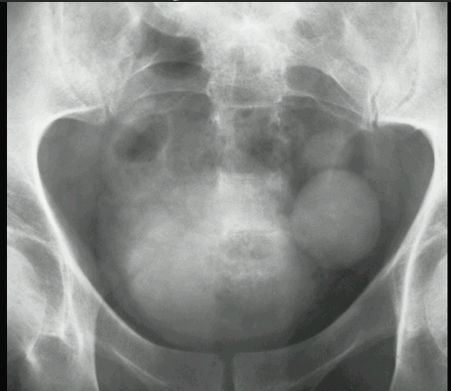

UCHYŁEK PĘCHERZA MOCZOWEGO

TK